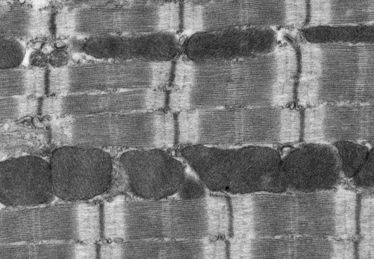

Münster (upm) - Damit das Herz richtig arbeiten kann, muss es Muskelkraft aufbringen. Dies geschieht, indem sich zahlreiche Sarkomere, die kleinsten Einheiten des Herzmuskels, verkürzen. Die hierzu notwendige Zugkraft basiert auf der Aktivität von klassischen Motorproteinen, die ihrerseits Proteinfäden des Sarkomers gegeneinander verschieben. Wissenschaftler der Universität Münster (WWU) haben nun in Kooperation mit Kollegen aus dem kanadischen Toronto und dem niederländischen Leiden mehr über die Funktion eines bestimmten Motorproteins herausgefunden, dem Myosin 18A, kurz: Myo18A. Sie entdeckten, dass eine neue Variante des Proteins für die mechanische Stabilisierung des Sarkomers im Herzen verantwortlich ist. Die Ergebnisse könnten dabei helfen, die Grundlagen des Herzmuskel-Aufbaus und dessen Kontraktion besser zu verstehen. Beteiligt an der Studie, die jetzt in der Fachzeitschrift „The Journal of Biological Chemistry“ erschien und darin als Forschungshöhepunkt („Editors’ Pick“) ausgezeichnet wurde, war auch das Institut für Pharmakologie und Toxikologie der Medizinischen Fakultät.

Schon vor ihren Forschungen hatten die Forscher vermutet, dass das Motorprotein Myosin 18A unter anderem für die Fortbewegung von Zellen wichtig ist. Dass es wie sein „Verwandter“, das Myosin 18B (Myo18B), für die Funktion des Herzmuskels eine kritische Rolle spielt, war aber bisher unbekannt. Mithilfe von sogenannten Genexpressionsanalysen beobachteten die Wissenschaftler: Das Gen, das das Protein Myo18A codiert, ist im Herzen von Mäusen während der Embryonalentwicklung in hohem Maße aktiv. Um die Funktion des Proteins zu bestimmen, schalteten die Wissenschaftler das Gen in Mäusen aus. Hierbei zeigte sich, dass diese Veränderung für die sich entwickelnden Embryonen tödlich war – genauso, wenn das Protein ausschließlich in der Herzmuskulatur ausgeschaltet war. „Das bedeutet im Umkehrschluss, dass das Protein eine wichtige Funktion für das Herz zu haben scheint“, sagt Biologe Dr. Peter Hanley, Gruppenleiter am Institut für Molekulare Zellbiologie der WWU.

In Kooperation mit Dr. Matthias Seidl vom Institut für Pharmakologie und Toxikologie der Medizinischen Fakultät der WWU zeigten die Wissenschaftler, dass eine bisher unbekannte, muskelspezifische Proteinvariante, Myo18Aγ, stark im Herzen exprimiert war – im Gegensatz zu den bereits bekannten Varianten Myo18Aa und Myo18b. Schalteten sie die neu entdeckte Proteinform genetisch aus, störte dies den Aufbau des Sarkomers.

„Unsere Ergebnisse zeigen, dass nicht nur das Myosin Myo18B, sondern auch Myo18A spezielle Funktionen im Sarkomer haben“, sagt Markus Horsthemke, Erstautor der Studie. Die Forscher vermuten, dass Myo18Aγ in erster Linie als Strukturprotein für die mechanische Stabilisierung des Sarkomers verantwortlich und nicht unmittelbar an der Kontraktion des Herzmuskels beteiligt ist.